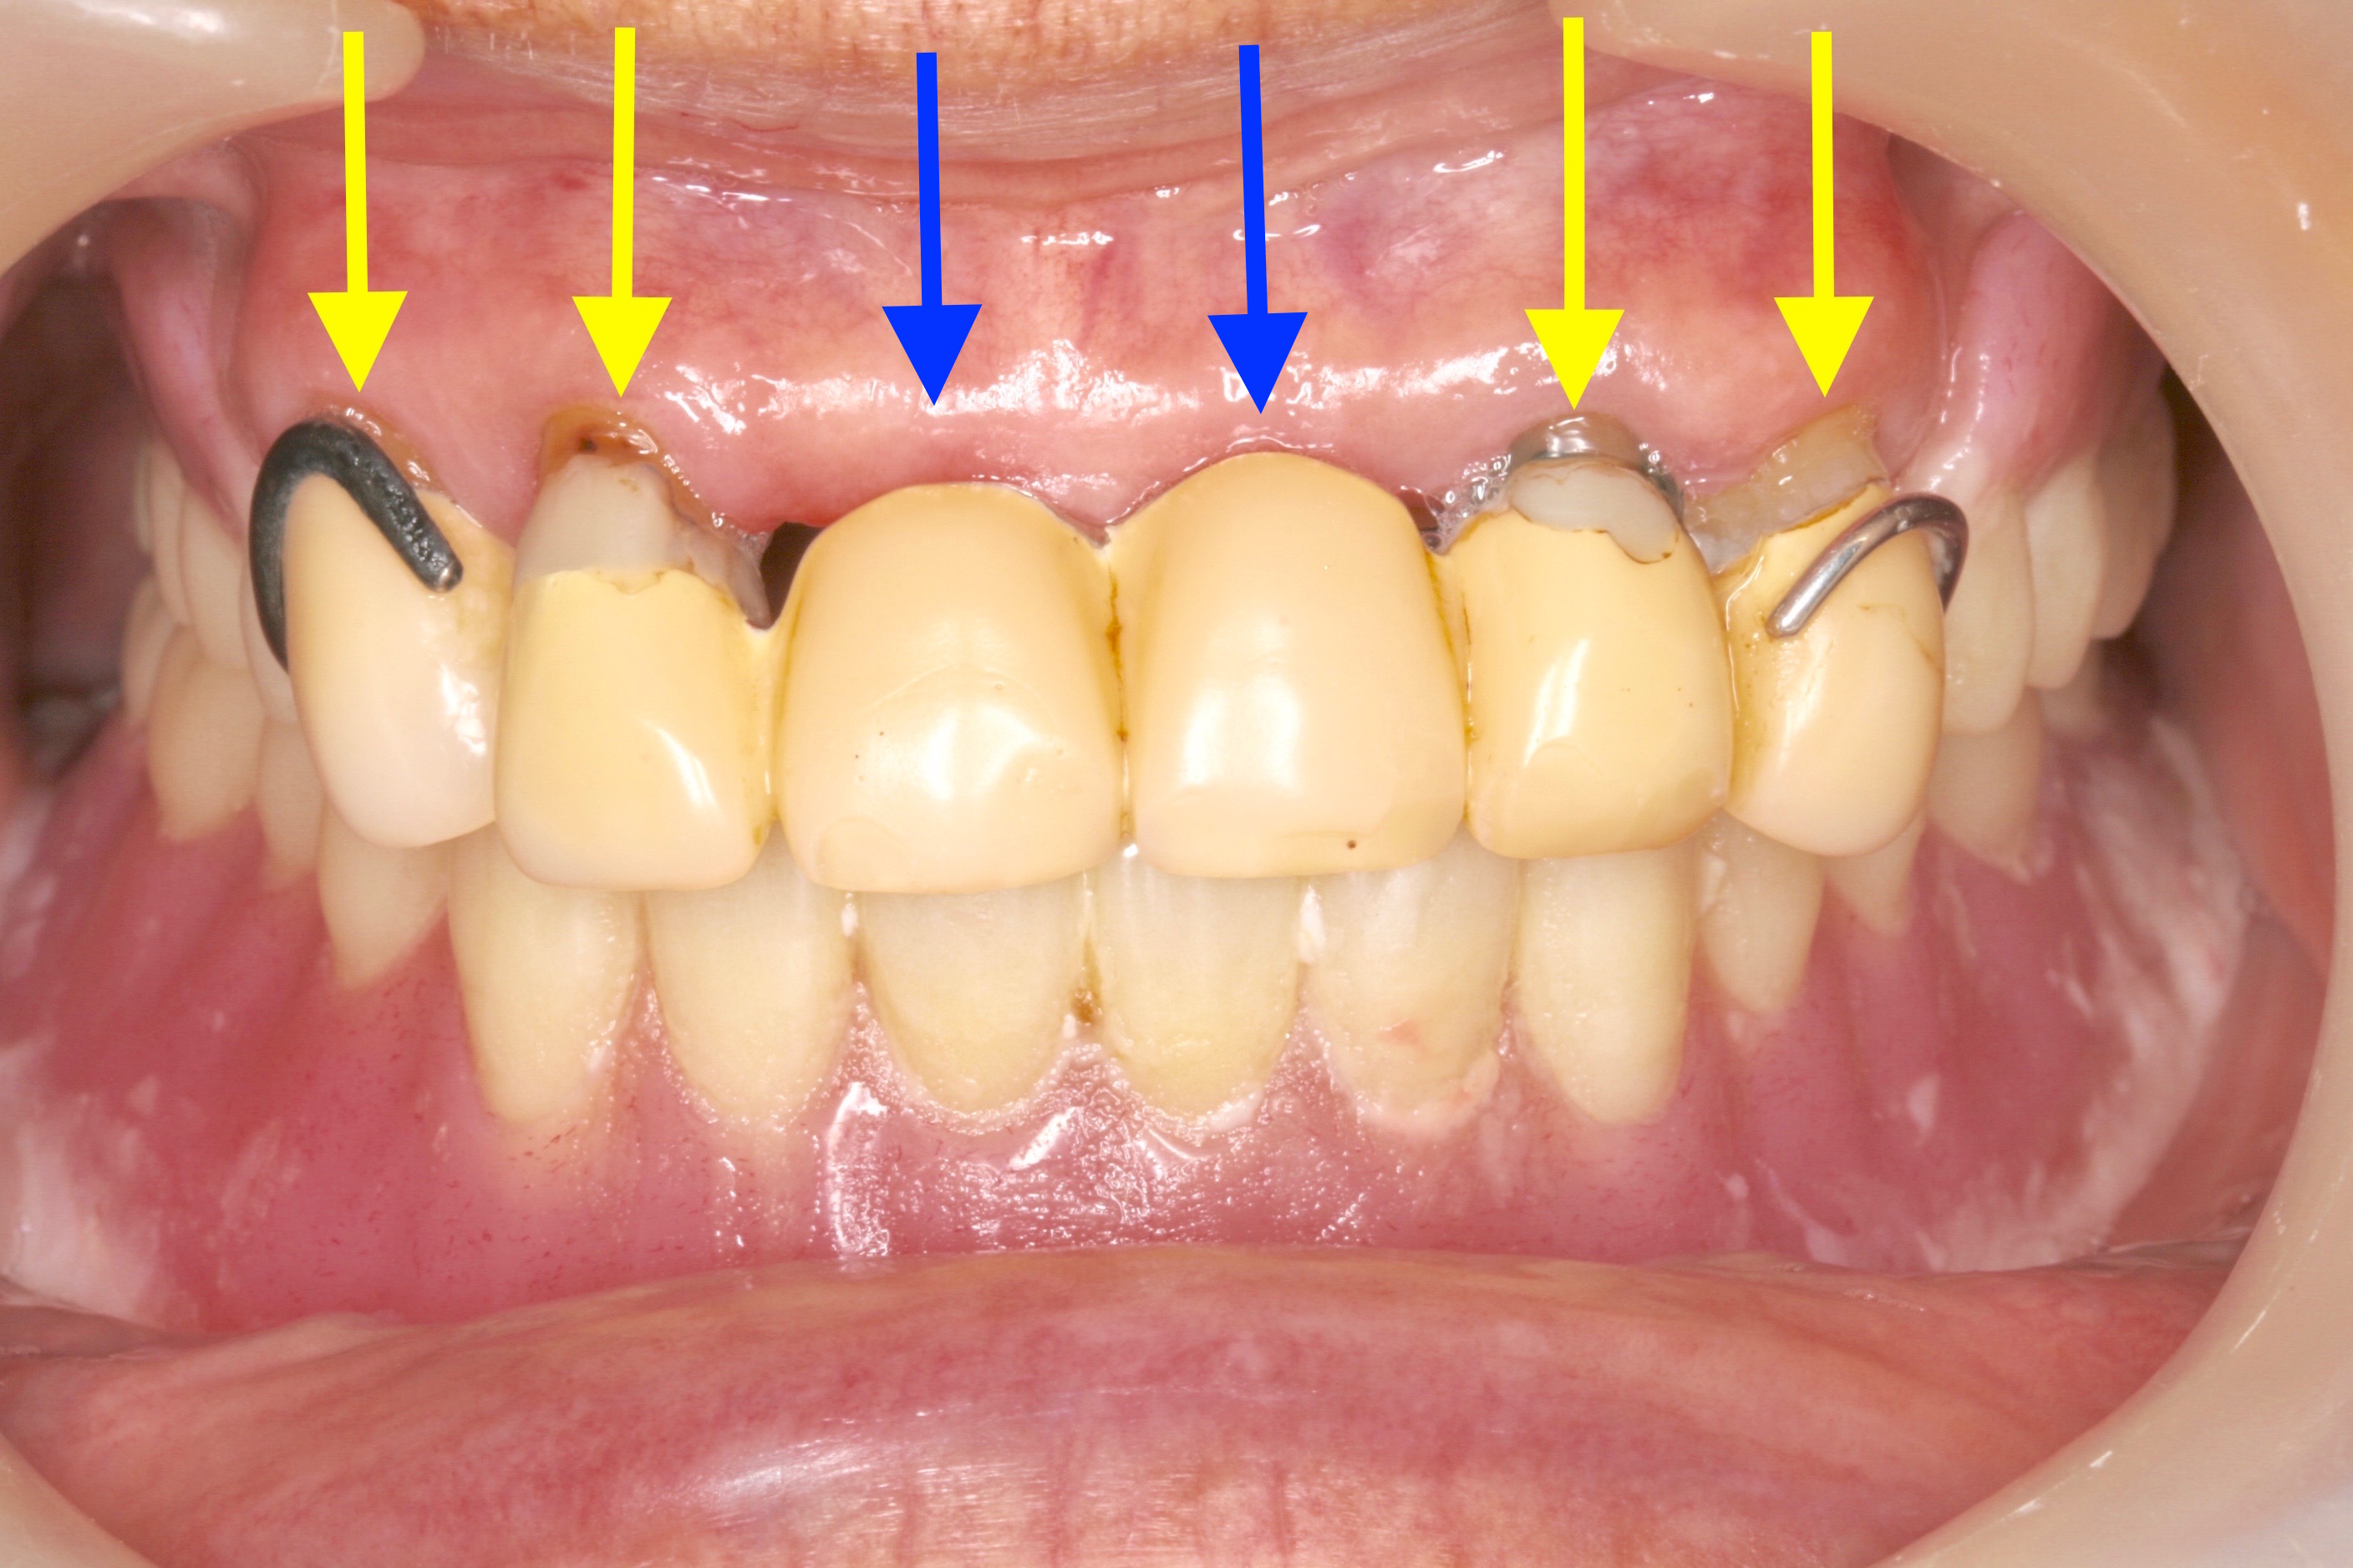

ケース NO.2 ⬆︎ 残した歯 ⬆︎ 抜いた歯

上がレジリエンツテレスコープ義歯、下が総入れ歯

この患者様は下アゴが分からない程痩せてしまっているため、

高度な技術が必要となります。